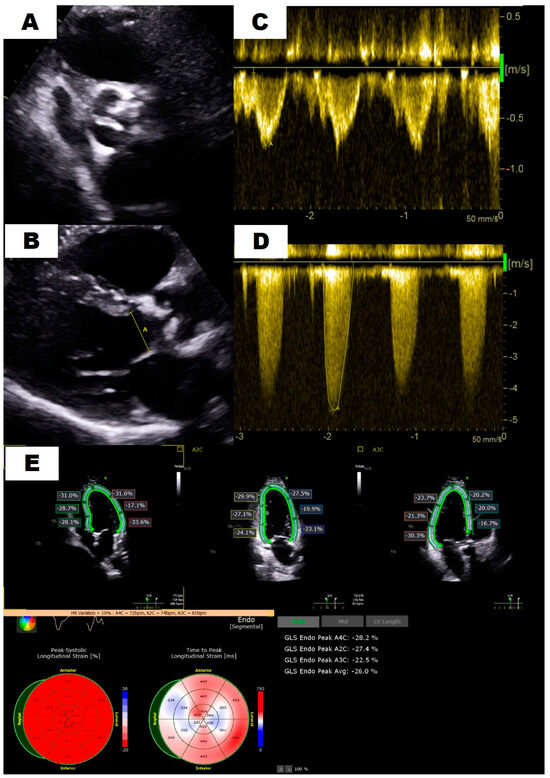

| Maximum velocity (m/s) | 4.3 ± 0.6 | 4.5 ± 0.4 | 3.4 ± 0.4 | <0.001 |

| Mean gradient (mm Hg) | 45 ± 13.3 | 49.3 ± 10.8 | 27.5 ± 6 | <0.001 |

| Aortic VTI (cm) | 99.2 ± 20.2 | 105.1 ± 16.9 | 75.3 ± 14.1 | <0.001 |

| LVOT VTI (cm) | 21.9 ± 8 | 22.9 ± 8.4 | 17.7 ± 4.2 | <0.001 |

| VTI ratio | 0.22 ± 0.06 | 0.22 ± 0.06 | 0.24 ± 0.05 | 0.04 |

| AVA (cm2) | 0.67 ± 0.17 | 0.66 ± 0.18 | 0.71 ± 0.13 | 0.048 |

| SV index (mL/m2) | 37.4 ± 10.5 | 39.6 ± 10.3 | 28.5 ± 4.8 | <0.001 |

| LVEF (%) | 62.3 ± 9.2 | 62 ± 9.7 | 63.6 ± 7.2 | 0.379 |

| IVS thickness (cm) | 1.31 ± 0.28 | 1.34 ± 0.27 | 1.22 ± 0.3 | 0.035 |

| PW thickness (cm) | 1.18 ± 0.23 | 1.2 ± 0.21 | 1.12 ± 0.27 | 0.069 |

| LVEDD (cm) | 4.35 ± 0.75 | 4.32 ± 0.77 | 4.47 ± 0.65 | 0.303 |